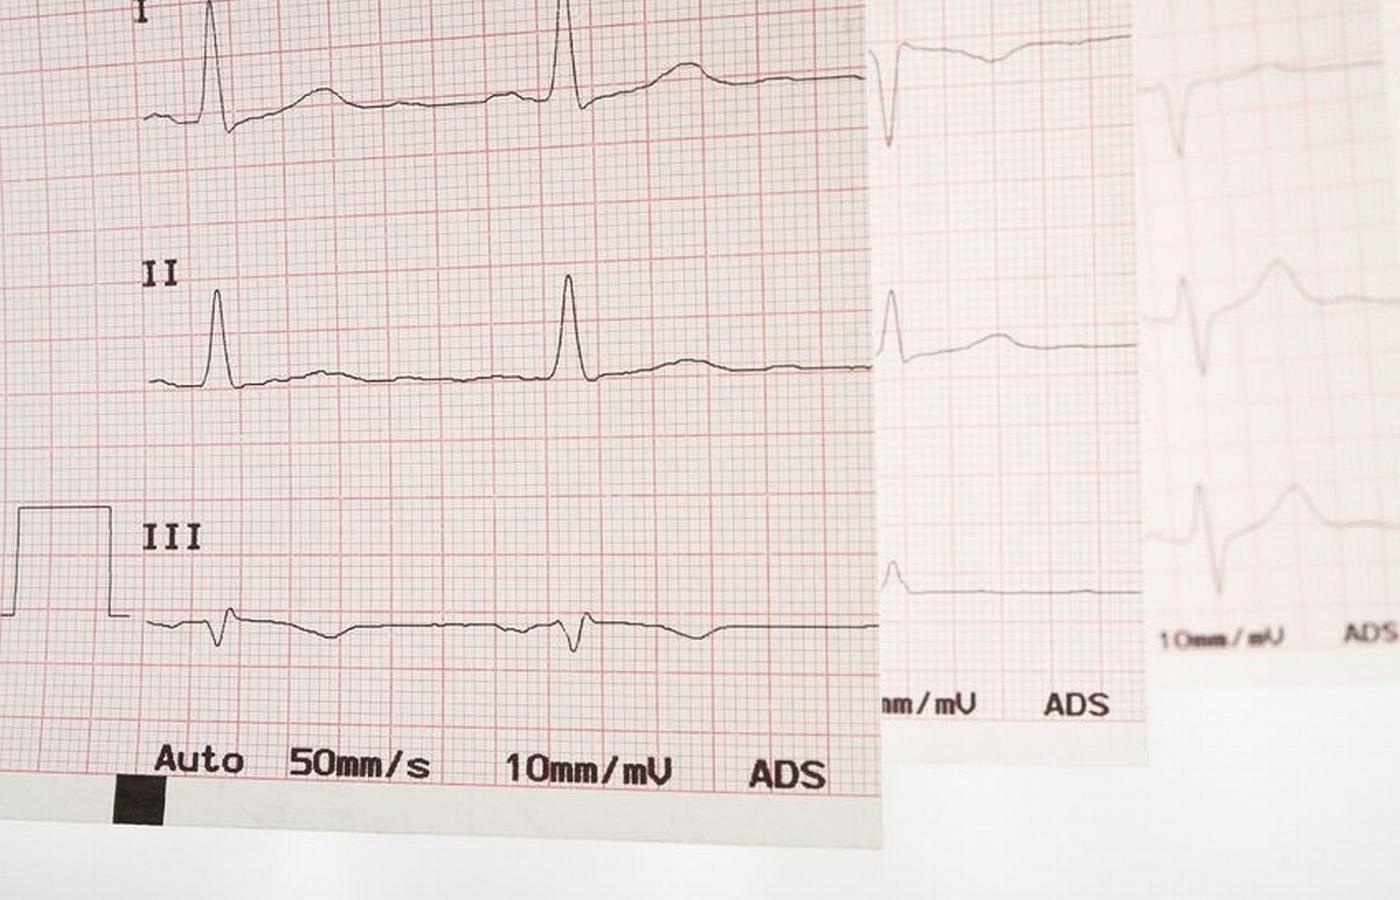

Powody niemiarowego bicia serca może wyjaśnić badanie EKG, lecz nie uchodzi ono za standard w gabinetach lekarzy rodzinnych. Powody niemiarowego bicia serca może wyjaśnić badanie EKG, lecz nie uchodzi ono za standard w gabinetach lekarzy rodzinnych. maurus / Smarterpix/PantherMedia

Spośród 400 tys. chorych co czwarty nawet nie wie, że powinien się leczyć (powody niemiarowego bicia serca i częstego zmęczenia może wyjaśnić badanie EKG, lecz nie uchodzi ono przecież za standard w gabinetach lekarzy rodzinnych). Dlatego z terapii korzysta raptem 215 tys. chorych, z których mniej niż 10 tys. leczy się nowoczesnymi preparatami. 160 tys. stosuje leki przeciwkrzepliwe starszej generacji, choć u 60 proc. tzw. współczynnik krzepliwości balansuje na granicy normy i w każdej chwili może wystąpić u nich niebezpieczny krwotok. Na tym polega trudność tej terapii: z jednej strony trzeba zabezpieczać chorego przed powstającymi wskutek migotania zakrzepami, z drugiej – nie dopuszczać do zbytniego rozrzedzenia krwi i zagrożenia krwawieniami. Niektórzy nie chcą podejmować tego ryzyka, więc się nie leczą – a sporadyczny kontakt z lekarzem w przychodni nie pozwala na to, by wyjaśnić wątpliwości i dobrać bezpieczną kurację.